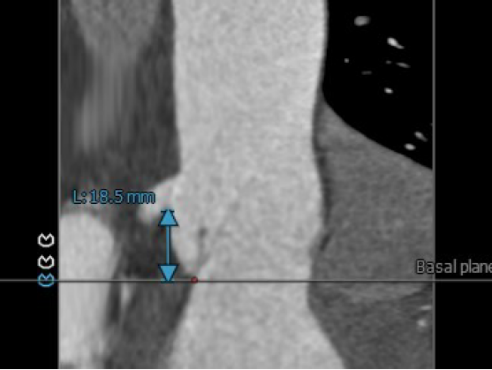

3.双侧冠脉开口高度可 LCA:18.5mm,RCA: 24.4mm;

左冠高度:18.5mm